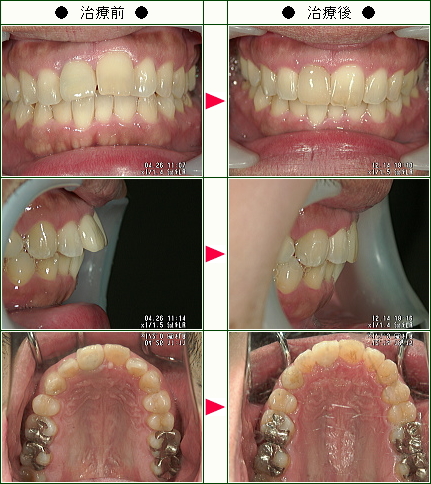

☆歯のデコボコ矯正症例(M様 31歳 女性)